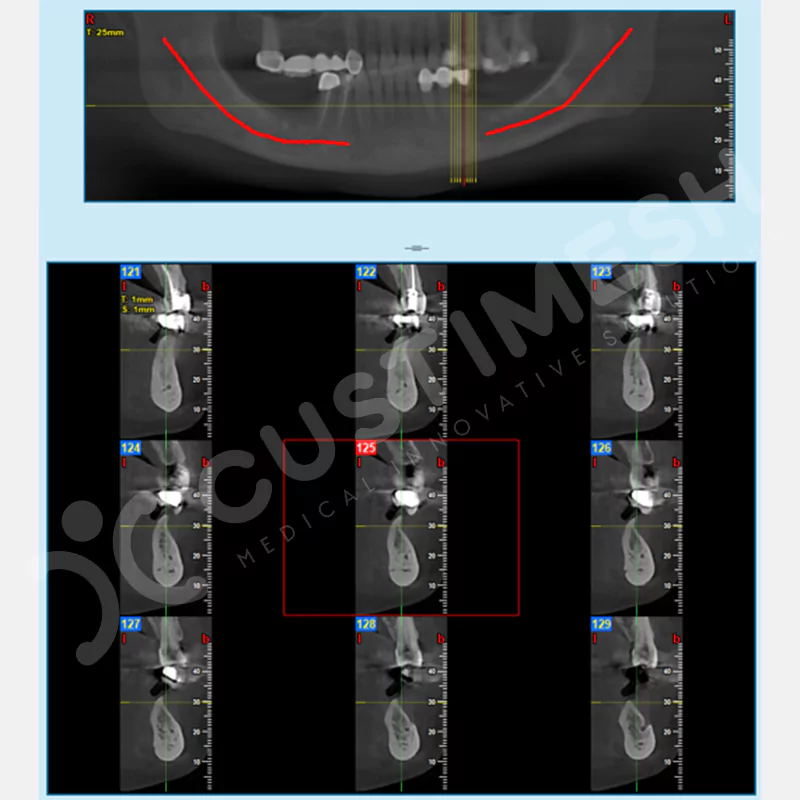

VAKA 3